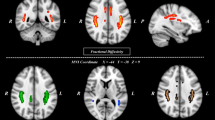

Figure 6 shows that all states have different distributions for degree. Only the most representative result is selected among 20 rat samples for each state. In general, SHR/low-ISO has more degrees and covers more brain regions than WKY/ high-ISO. The rank 1 in HS is the Primary motor cortex, while HW, LS, and LW the Secondary motor cortex. In the mean time, the rank 2 in HS is Retrosplenial agranular cortex, while HW, LS, and LW are Primary motor cortex. Whenever the brain develops disorder, it exhibits a different functional network that consequently gives rise to a new exponent for the power law in Fig. 1. This is similar to the finding of Ref.2 that the exponent may vary as the trial subject engages in different activities. We can find that the most active brain regions are the same. However, if we just focus on the samples of SHR, we discover that the secondary motor18 will fall to rank four. This is the reason why LS rat is more active than HS rat. More details will rely on more biological experiments in the future. The prefrontal cortex of ADHD patients has been reported to show abnormalities19,20. In our case, we can check two important regions in the prefrontal cortex to distinguish different states. These regions, Prl21,22,23,24 and Fra25, are related to the self-control and ADHD. The prefrontal cortex of SHR rat has been studied26,27,28. Figure 7A shows the summation of degree over whole brain region with 6 samples in 4 states, while Fig. 7B and C show the average number of node in Prl and Fra. Note that the stimulus interaction for LS being lower than LW in Fra is contrary to our expectation. Future biological experiments are needed to clarify the source of this problem.